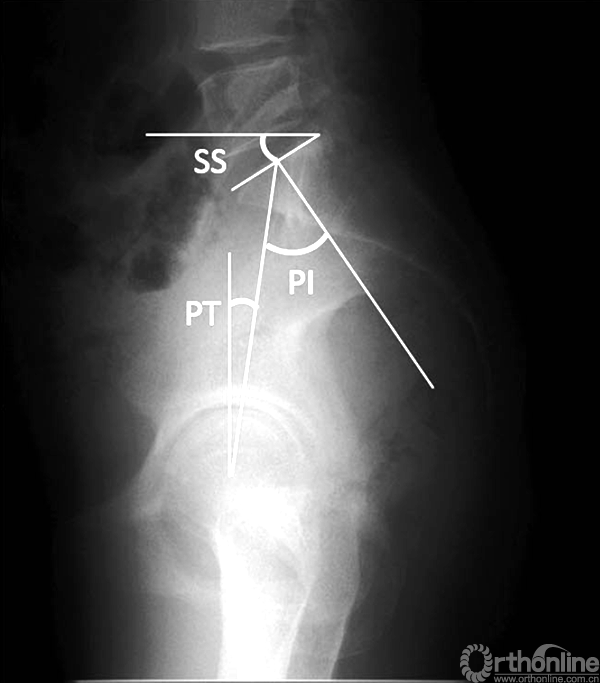

近10年来,脊柱骨盆矢状位平衡一直是脊柱外科的研究热点之一,围绕PI衍生出一系列的脊柱骨盆参数,其中最常用的包括骨盆倾斜度(pelvic tilt,PT)和骶骨倾斜角(sacral slope,SS)。骨盆相关参数与患者的健康相关生活质量(health-related quality of life,HRQOL)紧密相关[5]。

骨盆参数PI、PT、SS示意图

通过对健康人群的大样本测量分析,Schwab等[6]提出理想的腰椎前凸(lumbar lordosis,LL)与PI近似相等(LL = PI±9°)。而Jackson等[7]此前的研究结果则显示,正常情况下胸椎后凸(thoracic kyphosis,TK)与LL的比值TK/LL为0.15~0.75。

而理想的PT值tPT(theoretical normal pelvic tilt,tPT)=0.37*PI-7°[8]。因此,通过测量患者术前的PI值,我们可以推导出相对理想的矢状位曲线。例如对于一个PI值为45°的患者,其理想的LL为45°,其中下腰椎LL为30°,TK应<35°,tPT=10°。